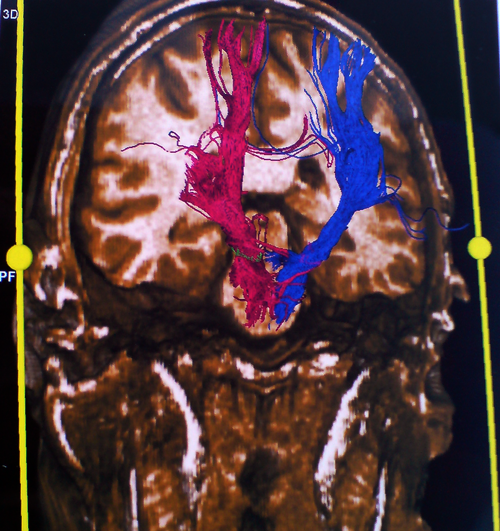

Στο μοντέλο αυτό μπορούν να συνεισαχθούν και πληροφορίες από άλλες ακολουθίες της μαγνητικής τομογραφίας, π.χ. λειτουργικές ακολουθίες όπου απεικονίζονται θέσεις κέντρων του λόγου ή της κίνησης ή ακολουθίες δεσμιδογραφίας όπου απεικονίζονται νευρικές οδοί στο βάθος του εγκεφάλου. Ο χειρουργός έχει έτσι την δυνατότητα να σχεδιάσει προεγχειρητικά την επέμβαση, αποφεύγοντας για παράδειγμα προσπελάσεις που αυξάνουν τον κίνδυνο τραυματισμού ευγενών περιοχών του εγκεφάλου ή μεγάλων αγγείων. Η ταύτιση του ψηφιακού μοντέλου με τον προεγχειρητικό σχεδιασμό και της πραγματικής ανατομίας γίνεται στο χειρουργείο με την

Δεσμιδογραφία (DT MRI) εγκεφάλου

Navi6

βοήθεια ειδικού εξοπλισμού και το τελικό αποτέλεσμα προβάλλεται στην οθόνη του νευροπλοηγού και στο χειρουργικό μικροσκόπιο καθ' όλη τη διάρκεια της χειρουργικής παρέμβασης.